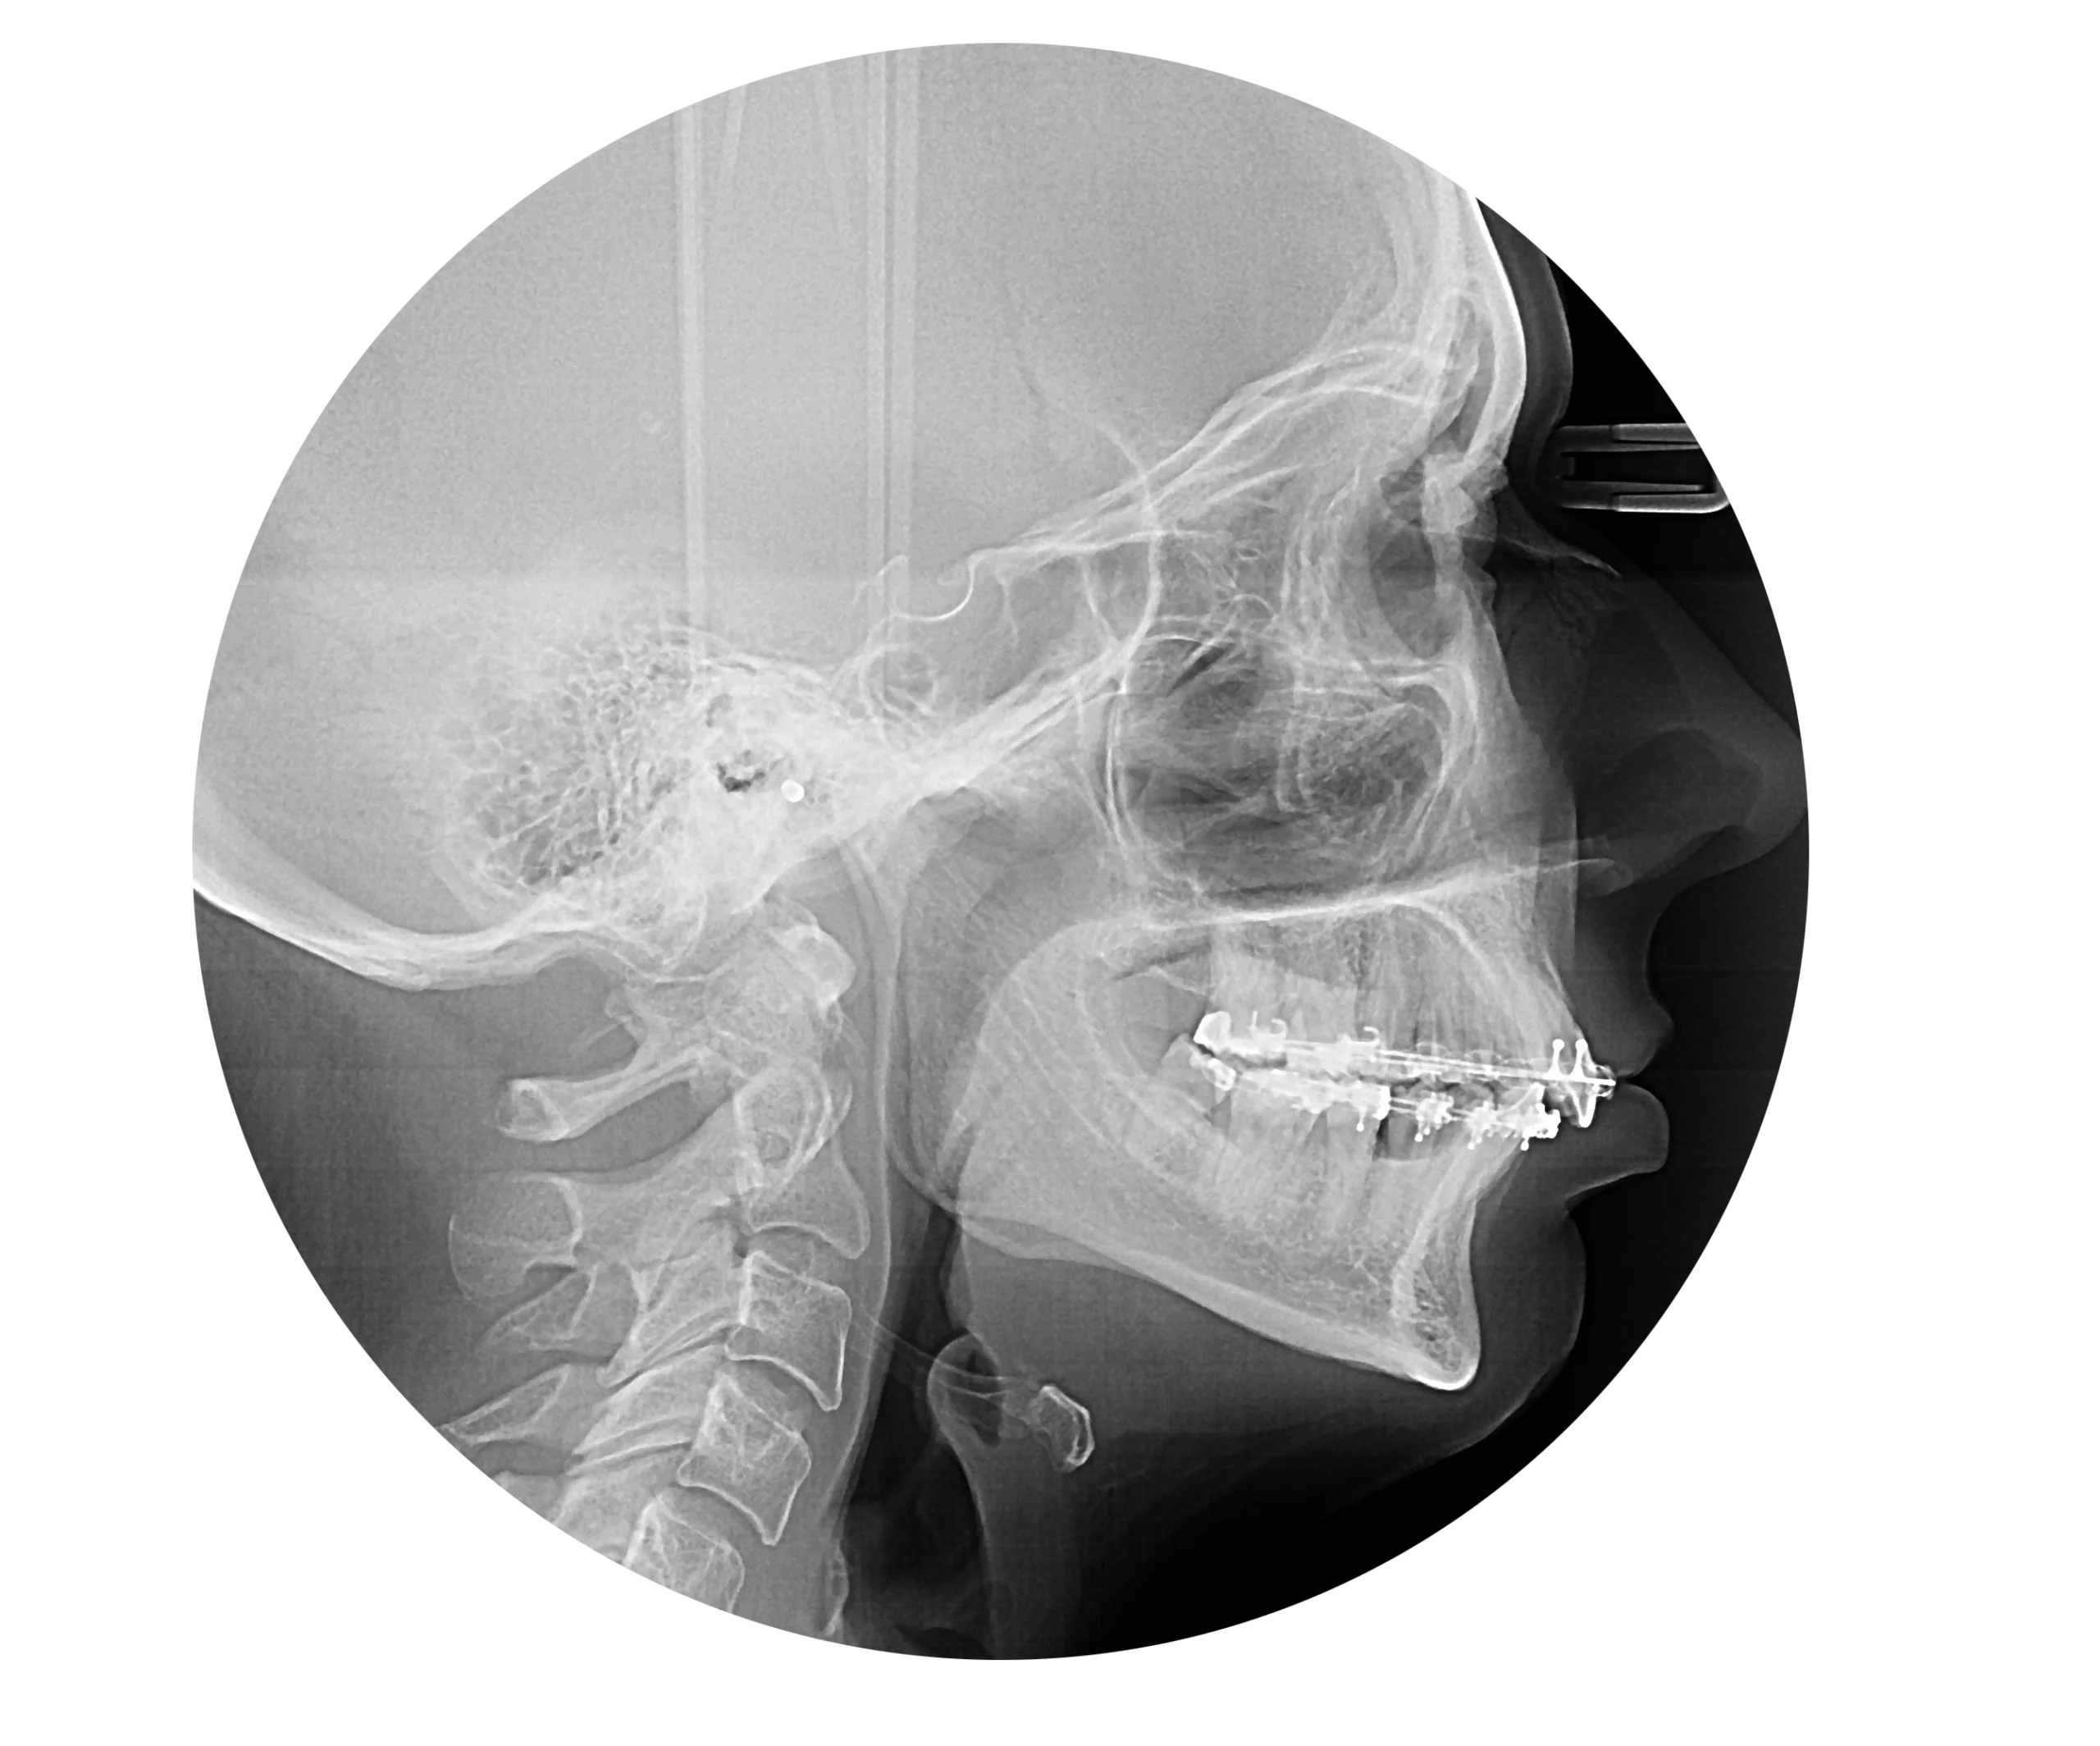

風險評估及注意事項

在進行不手術矯正前,必須由牙科矯正專科醫師進行全面評估,包含:

顱顏 X 光( 側位頭影測量 )

判斷骨性與牙性問題比例

全口 X 光

檢查牙根、牙周狀況與阻生牙